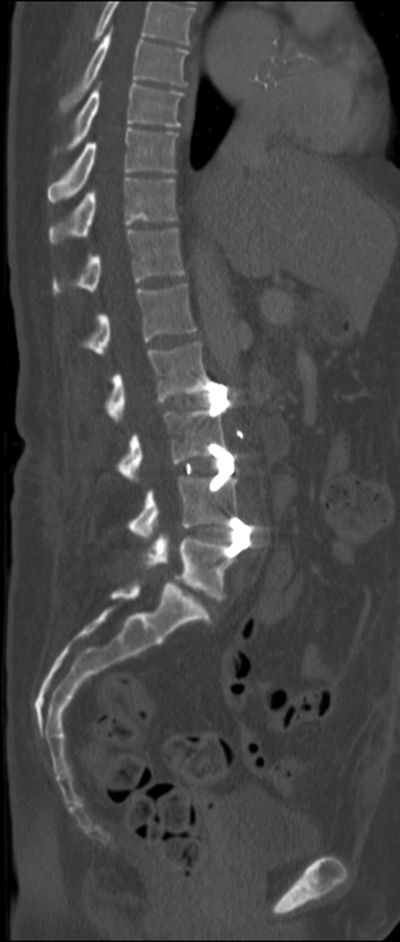

A variation of vertebroplasty is kyphoplasty, which uses a balloon that is inflated in the treated vertebral body to create a cavity within the vertebral cancellous bone (figure: kyphoplasty systems). The vertebroplasty cement is instilled directly into the newly created cavity after the balloon is deflated. Kyphoplasty and vertebroplasty have similar outcomes. Kyphoplasty is somewhat more expensive, but it can sometimes restore the height of the central aspect of the vertebral body by as much as 3 mm (Petscavage-Thomas, 2014). It is sometimes used for kyphotic deformity correction or in more complex cases of vertebral injury (McConnell, 2014).

Vertebroplasty volumes and rates decreased sharply after 2009. There is a trend toward more kyphoplasty which has somewhat offset the decrease in volume of vertebroplasty procedures (Cox, 2016). The 2020 study by Hinde showed kyphoplasty outperformed vertebroplasty on mortality. This may be from improved pulmonary function as the result of restoration of vertebral height as well as possible improved mobility (Hinde, 2020).

Kyphoplasty |

Vertebral Body Balloon (VBB) System (DePuy Synthes) for vertebral augmentation procedures (kyphoplasty). © DePuy Synthes 2016. All rights reserved. Vertebral Body Balloon (VBB) System is a trademark of DePuy Synthes. |

Confidence Spinal Cement System for kyphoplasty. © DePuy Synthes 2016. All rights reserved. CONFIDENCE SPINAL CEMENT SYSTEM® is a trademark of DePuy Synthes. |